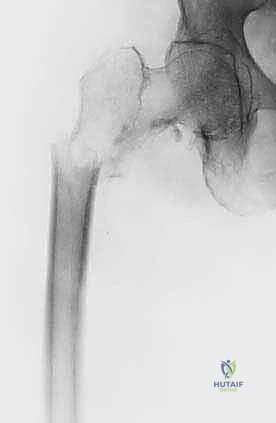

1. التثبيت الوقائي الداخلي (Prophylactic Internal Fixation)

إذا أظهرت الأشعة أن العظم ضعيف جداً وعلى وشك الانكسار، يقوم الدكتور هطيف بوضع أسياخ نخاعية معدنية (Intramedullary Nails) أو شرائح ومسامير متطورة داخل العظم لتدعيمه ومنع الكسر قبل حدوثه. هذه الجراحة الاستباقية توفر على المريض آلاماً مبرحة ومضاعفات خطيرة.